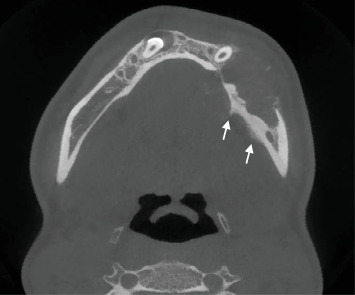

骨肉瘤是最常见的原发性骨恶性肿瘤,很少影响颌骨,仅占病例的6%-10%。颌骨骨肉瘤通常发生在30至50岁之间的个体中,在儿童中并不常见。它通常累及下颌骨,尤其是男性,表现为肿胀、牙齿活动和感觉异常,而不是疼痛。我们提出一个罕见的颌骨骨肉瘤病例在一个12岁的女孩谁表现出感觉异常和显著下颌骨肿块。影像学显示广泛的下颌骨累及Codman三角区,活检证实了常规骨肉瘤的诊断。治疗方法包括半下颌管切除术,随后使用钛板和橡胶垫片进行临时重建。本病例强调了综合评估和多学科管理在儿童颌骨骨肉瘤诊断和治疗中的重要性。对12例类似病例的回顾强调了表现和治疗结果的可变性,强调了个性化治疗计划以优化患者预后的必要性。

Osteosarcoma, the most common primary bone malignancy, rarely affects the jaw, representing only 6%-10% of cases. Jaw osteosarcoma typically occurs in individuals between the ages of 30 and 50 years and is uncommon in children. It often involves the mandible, especially in males, presenting with swelling, tooth mobility, and paraesthesia rather than pain. We present a rare case of jaw osteosarcoma in a 12-year-old girl who exhibited paraesthesia and a significant mandibular mass. Imaging demonstrated extensive mandibular involvement with Codman's triangle formation, and a biopsy confirmed the diagnosis of conventional osteosarcoma. The treatment approach included a hemimandibulectomy, followed by temporary reconstruction using a titanium plate and silastic spacer. This case underscores the importance of comprehensive evaluation and multidisciplinary management in diagnosing and treating osteosarcoma of the jaws in children. A review of 12 similar cases highlights the variability in presentation and treatment outcomes, emphasizing the need for individualized treatment plans to optimize patient prognosis.